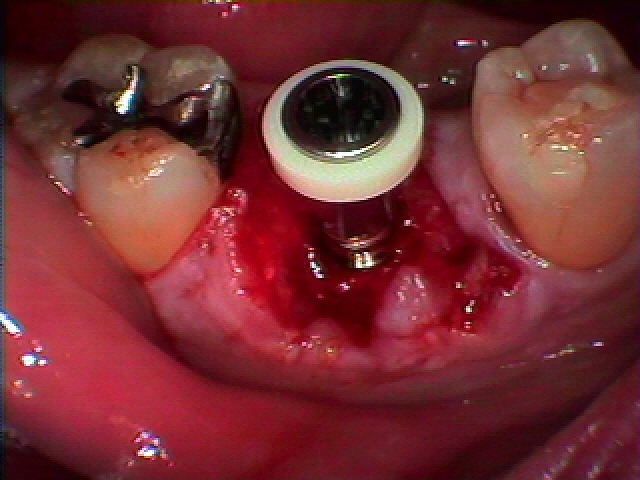

インプラント埋入時になります

インプラント埋入時になります

5mmの11,5mmというインプラントを埋入しています